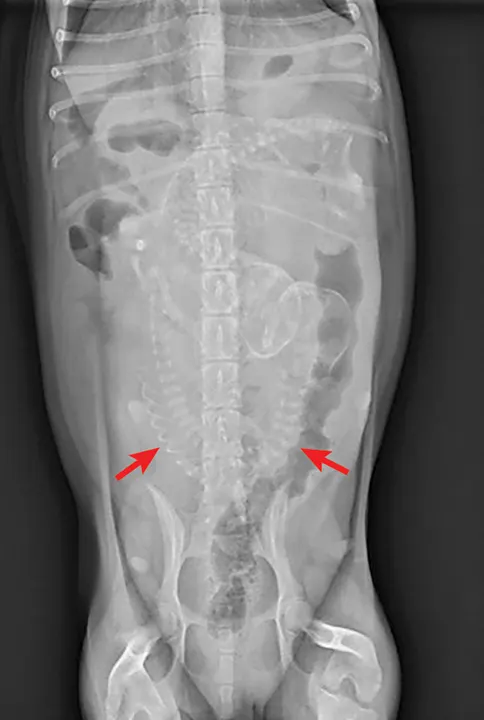

FIGURE 1

Ventrodorsal abdominal radiograph of a pregnant bitch presenting for dystocia. Note the malpositioned fetus oriented transversely to the pelvic canal. Radiographs courtesy of Amanda A. Cavanagh, DVM, DACVECC

If the bitch is examined after day 44 of gestation, when fetal skeletons mineralize, radiographs should be obtained to determine litter size, fetal positioning, and signs of fetal death.2,8 (See Figure 1 & Figure 2.) Ultrasonography is the ideal imaging modality for determining fetal stress and viability.2